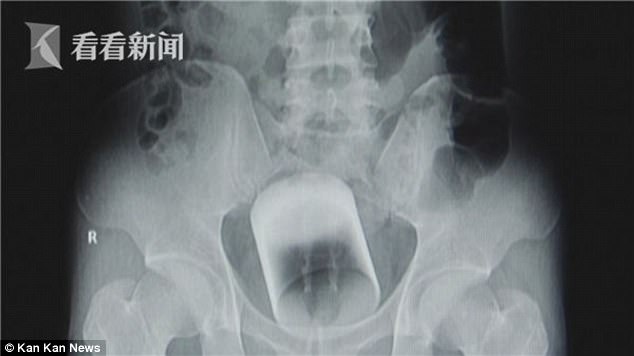

An X-ray showed a tumbler was stuck in Xiao Zhang’s rectum. It measured 3.15 inches (eight centimetres) tall and 2.8 inches (seven centimetres) wide.

Dr. Cai Yonghua, a specialist in colorectal and anal surgery, said stated that the glass tumbler was located in the upper to middle section of the rectum.

The cup was stuck about seven centimetres (2.8 inches) into the rectum.